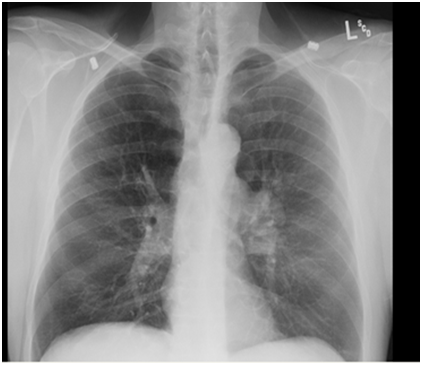

MRI abdomen done-innumerable hepatic masses suspicious for hepatic metastasis or multifocal hepatocellular carcinoma with hepatic cirrhosis. Patient was planned for CT guided liver biopsy. Vitamin K and FFP were administered overnight.

MRI abdomen

Figure 3

Figure 3 MRI abdomen.